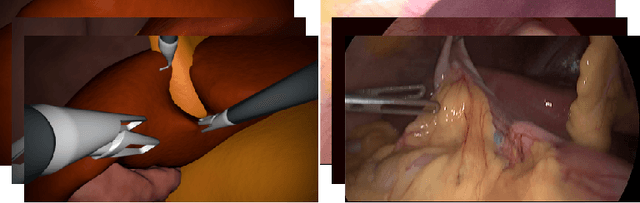

Abstract:In the medical domain, the lack of large training data sets and benchmarks is often a limiting factor for training deep neural networks. In contrast to expensive manual labeling, computer simulations can generate large and fully labeled data sets with a minimum of manual effort. However, models that are trained on simulated data usually do not translate well to real scenarios. To bridge the domain gap between simulated and real laparoscopic images, we exploit recent advances in unpaired image-to-image translation. We extent an image-to-image translation method to generate a diverse multitude of realistically looking synthetic images based on images from a simple laparoscopy simulation. By incorporating means to ensure that the image content is preserved during the translation process, we ensure that the labels given for the simulated images remain valid for their realistically looking translations. This way, we are able to generate a large, fully labeled synthetic data set of laparoscopic images with realistic appearance. We show that this data set can be used to train models for the task of liver segmentation of laparoscopic images. We achieve average dice scores of up to 0.89 in some patients without manually labeling a single laparoscopic image and show that using our synthetic data to pre-train models can greatly improve their performance. The synthetic data set will be made publicly available, fully labeled with segmentation maps, depth maps, normal maps, and positions of tools and camera (http://opencas.dkfz.de/image2image).